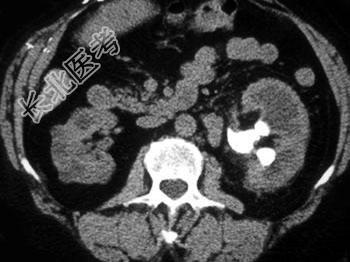

- 双肾CT平扫图像如下,符合下列何种疾病